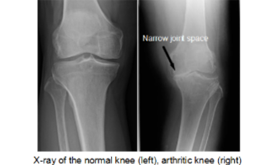

In osteoarthritis, the cartilage in the knee joint gradually wears away. As the cartilage wears away, it becomes frayed and rough, and the protective space between the bones decreases. This can result in bone rubbing on bone, and hence cause pain.

Your surgeon will perform a detailed physical examination and may request you to undergo imaging studies like X-rays and ocassionally a MRI or a bone scan.